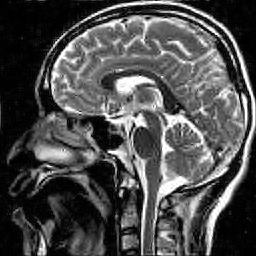

| Original image | Gauss. to DB4, err=31.54% | Gauss. to Flip DB4, err=31.51% |

| Subsampling pattern | DFT to DB4, err=10.96% | DFT to Flipped DB4, err=99.3% |

Since it will become important later, we now describe a quick and simple test, which we call the flip test, to investigate the presence or absence of an RIP. Success of this test suggests the existence of an RIP and failure demonstrates its lack.

Hence both and should recover equally well. In the top row of Figure 1 we present the result of the flip test for a Gaussian random matrix. As is evident, the reconstructions and are comparable, thus indicating the RIP.

Having considered type II problems, let us now examine the flip test for a type I problem. As discussed, in applications such as MRI, X-ray CT, radio interferometry, etc, the matrix is imposed by the physical sensing device and arises from subsampling the rows of the DFT matrix .111In actual fact, the sensing device takes measurements of the continuous Fourier transform of a function . As discussed in BAACHGSCS ; BAGSAIEP , modelling continuous Fourier measurements as discrete Fourier measurements can lead to inferior reconstructions, and worse, inverse crimes. To avoid this, one must consider an infinite-dimensional compressed sensing approach, as in (2). See AHPRBreaking ; BAGSAIEP for details, as well as PruessmannUnserMRIFast for implementation in MRI. However, for simplicity, we shall continue to work with the finite-dimensional model in the remainder of this paper. Whilst one often has some freedom to choose which rows to sample (corresponding to selecting particular frequencies at which to take measurements), one cannot change the matrix .

It is well known that in order to ensure a good reconstruction, one cannot subsample the DFT uniformly at random (recall that the sparsifying transform is a wavelet basis), but rather one must sample randomly according to an appropriate nonuniform density AHPRBreaking ; Candes_Romberg ; Lustig ; WangAcre . See the bottom left panel of Figure 1 for an example of a typical density. As can be seen in the next panel, by doing so one achieves a great recovery. However, the result of the flip test in the bottom right panel clearly demonstrates that the matrix does not satisfy an RIP. In particular, the ordering of the wavelet coefficients plays a crucial role in the reconstruction quality. To explain this, and in particular, the high-quality reconstruction seen in the unflipped case, one evidently requires a new analytical framework.

Note that the flip test in Figure 1 also highlights another important phenomenon: namely, the effectiveness of the subsampling strategy depends on the sparsity structure of the image. In particular, two images with the same total sparsity (the original and the flipped ) result in wildly different errors when the same sampling pattern is used. Thus we conclude that there is no one optimal sampling strategy for all sparse vectors of wavelet coefficients.